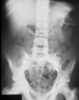

Sickle cell disease with bone infarction